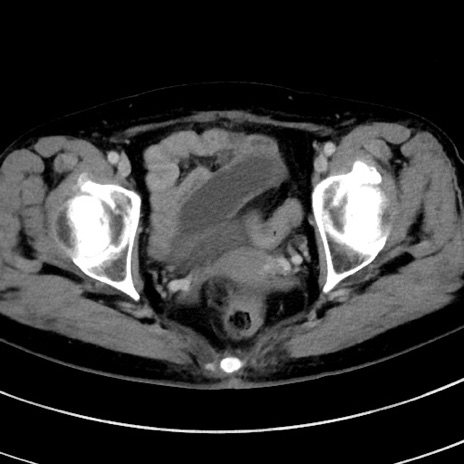

症例9(横断像)

【症例】 60歳代女性

【主訴】むかつき、みぞおちの痛み

【現病歴】3日前よりむかつきがあり、食事がとれない。

【既往歴】糖尿病

【身体所見】発熱なし、心窩部圧痛軽度あるも、腹膜刺激症状なし。

【データ】WBC 7400、CRP 1.92